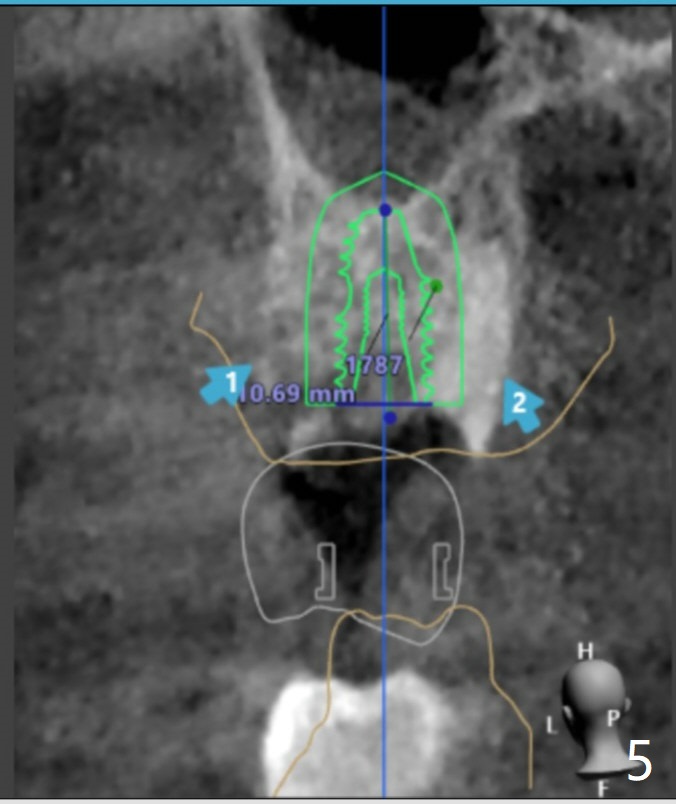

The FC implant will be placed more buccal (compare Fig.5-7).  Sinus lift is required most likely.

Upper Molar Immediate Implant Shield Trajectory II Shield Xin Wei, DDS, PhD, MS 1st edition 10/30/2019, last revision 02/21/2021